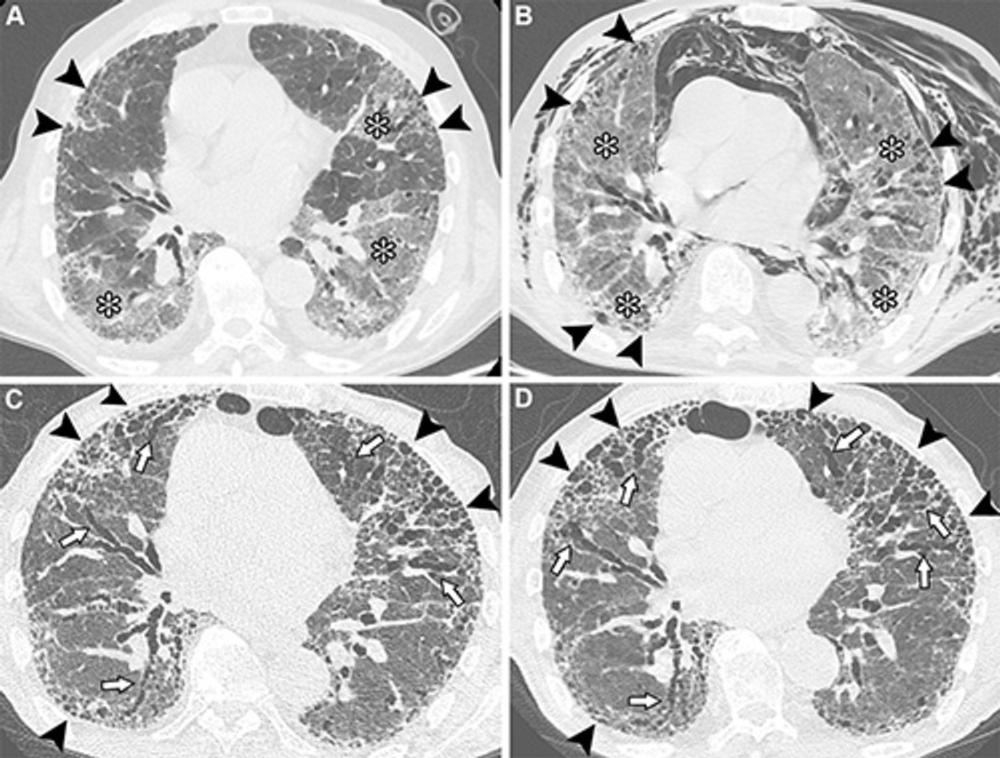

Figure 1. Unenhanced axial CT images show post–COVID-19 residual abnormalities in a 69-year-old male patient with a history of smoking and myocardial infarction. (A) Baseline image obtained at admission to intensive care department shows extensive ground-glass opacities and mild bilateral consolidation (black arrowheads), associated with crazy paving pattern (white arrowheads), spontaneous pneumomediastinum (*), and bilateral anterior chest wall subcutaneous emphysema. (B) Image obtained 1 month later shows complete resolution of the pneumomediastinum and subcutaneous emphysema, with persistent diffuse bilateral ground-glass opacities and reticular opacities. Mild lung and bronchial architectural distortion are also observed (arrows). The patient was discharged with instructions to use supplemental oxygen during exertion and at night. (C) Image obtained 4 months from baseline shows the reduction of prior ground-glass opacities and reticular opacities, with residual patchy areas of mild ground-glass opacities and fine reticular opacities showing subpleural and peribronchovascular distribution (arrowheads) in both lungs. Previously observed bronchial dilation shows improvement. The patient reported persistent mild exertional dyspnea, and pulmonary function tests revealed a mild restrictive pattern and slightly reduced diffusing lung capacity for carbon monoxide. (D) Image obtained at 1-year follow-up shows near-complete resolution of post–COVID-19 lung abnormalities, with only minimal residual ground-glass opacities and mild architectural distortion (arrowheads).